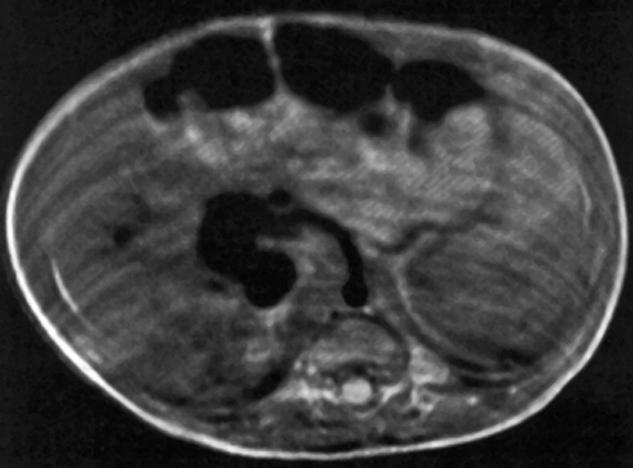

Figure 14-03:

Patient with hydrocephalus. On this T2-weighted SE image, CSF should be bright. How­ever, due to flow ef­fects, CSF in the aqueduct and the upper fourth ventricle appears dark.